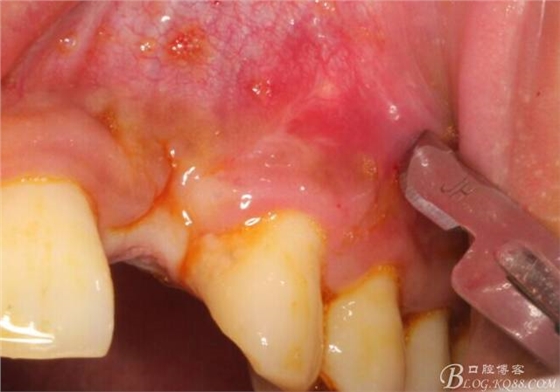

10天拆線一切正常,又過了兩周患者復(fù)診,自述期間無異常??趦?nèi)檢查,真的嚇了一跳,唇側(cè)鼓了個包,擠壓有白色分泌物溢出,絕對不是膿液,液體排除后,術(shù)區(qū)觸診空虛,外觀塌陷。這時候考研大夫的時刻到了,是先觀察一段時間再說?還是馬上進(jìn)行處理?我的回答是:馬上處理!如果你沒有及時處理,而是放患者回家觀察,那么接下來會發(fā)生如下情況:1.回家后患者家屬及親友會有很多你可以想象得到的討論;2.患者及家屬會對你產(chǎn)生不信任,勢必會到其他門診或醫(yī)院檢查,他院大夫會不會發(fā)表對你不利的言論;3甚至?xí)蚁嚓P(guān)法律界人士找你討要說法。

于是我果斷告知患者,手術(shù)失敗了,不能拖延,如不及時處理,炎癥繼續(xù)發(fā)展會很快波及鄰牙牙槽骨。患者接受我的建議。切開翻瓣,骨粉及生物膜消失了,骨吸收嚴(yán)重,幸運的是,因為處理及時,鄰牙骨支持依然存在。